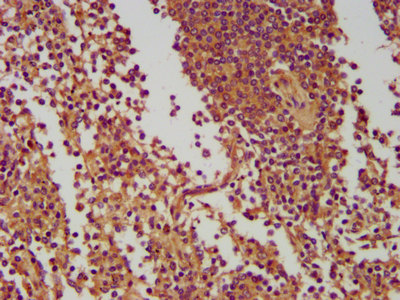

IHC image of CSB-PA771457LA01HU diluted at 1:400 and staining in paraffin-embedded human lung tissue performed on a Leica BondTM system. After dewaxing and hydration, antigen retrieval was mediated by high pressure in a citrate buffer (pH 6.0). Section was blocked with 10% normal goat serum 30min at RT. Then primary antibody (1% BSA) was incubated at 4°C overnight. The primary is detected by a biotinylated secondary antibody and visualized using an HRP conjugated SP system.